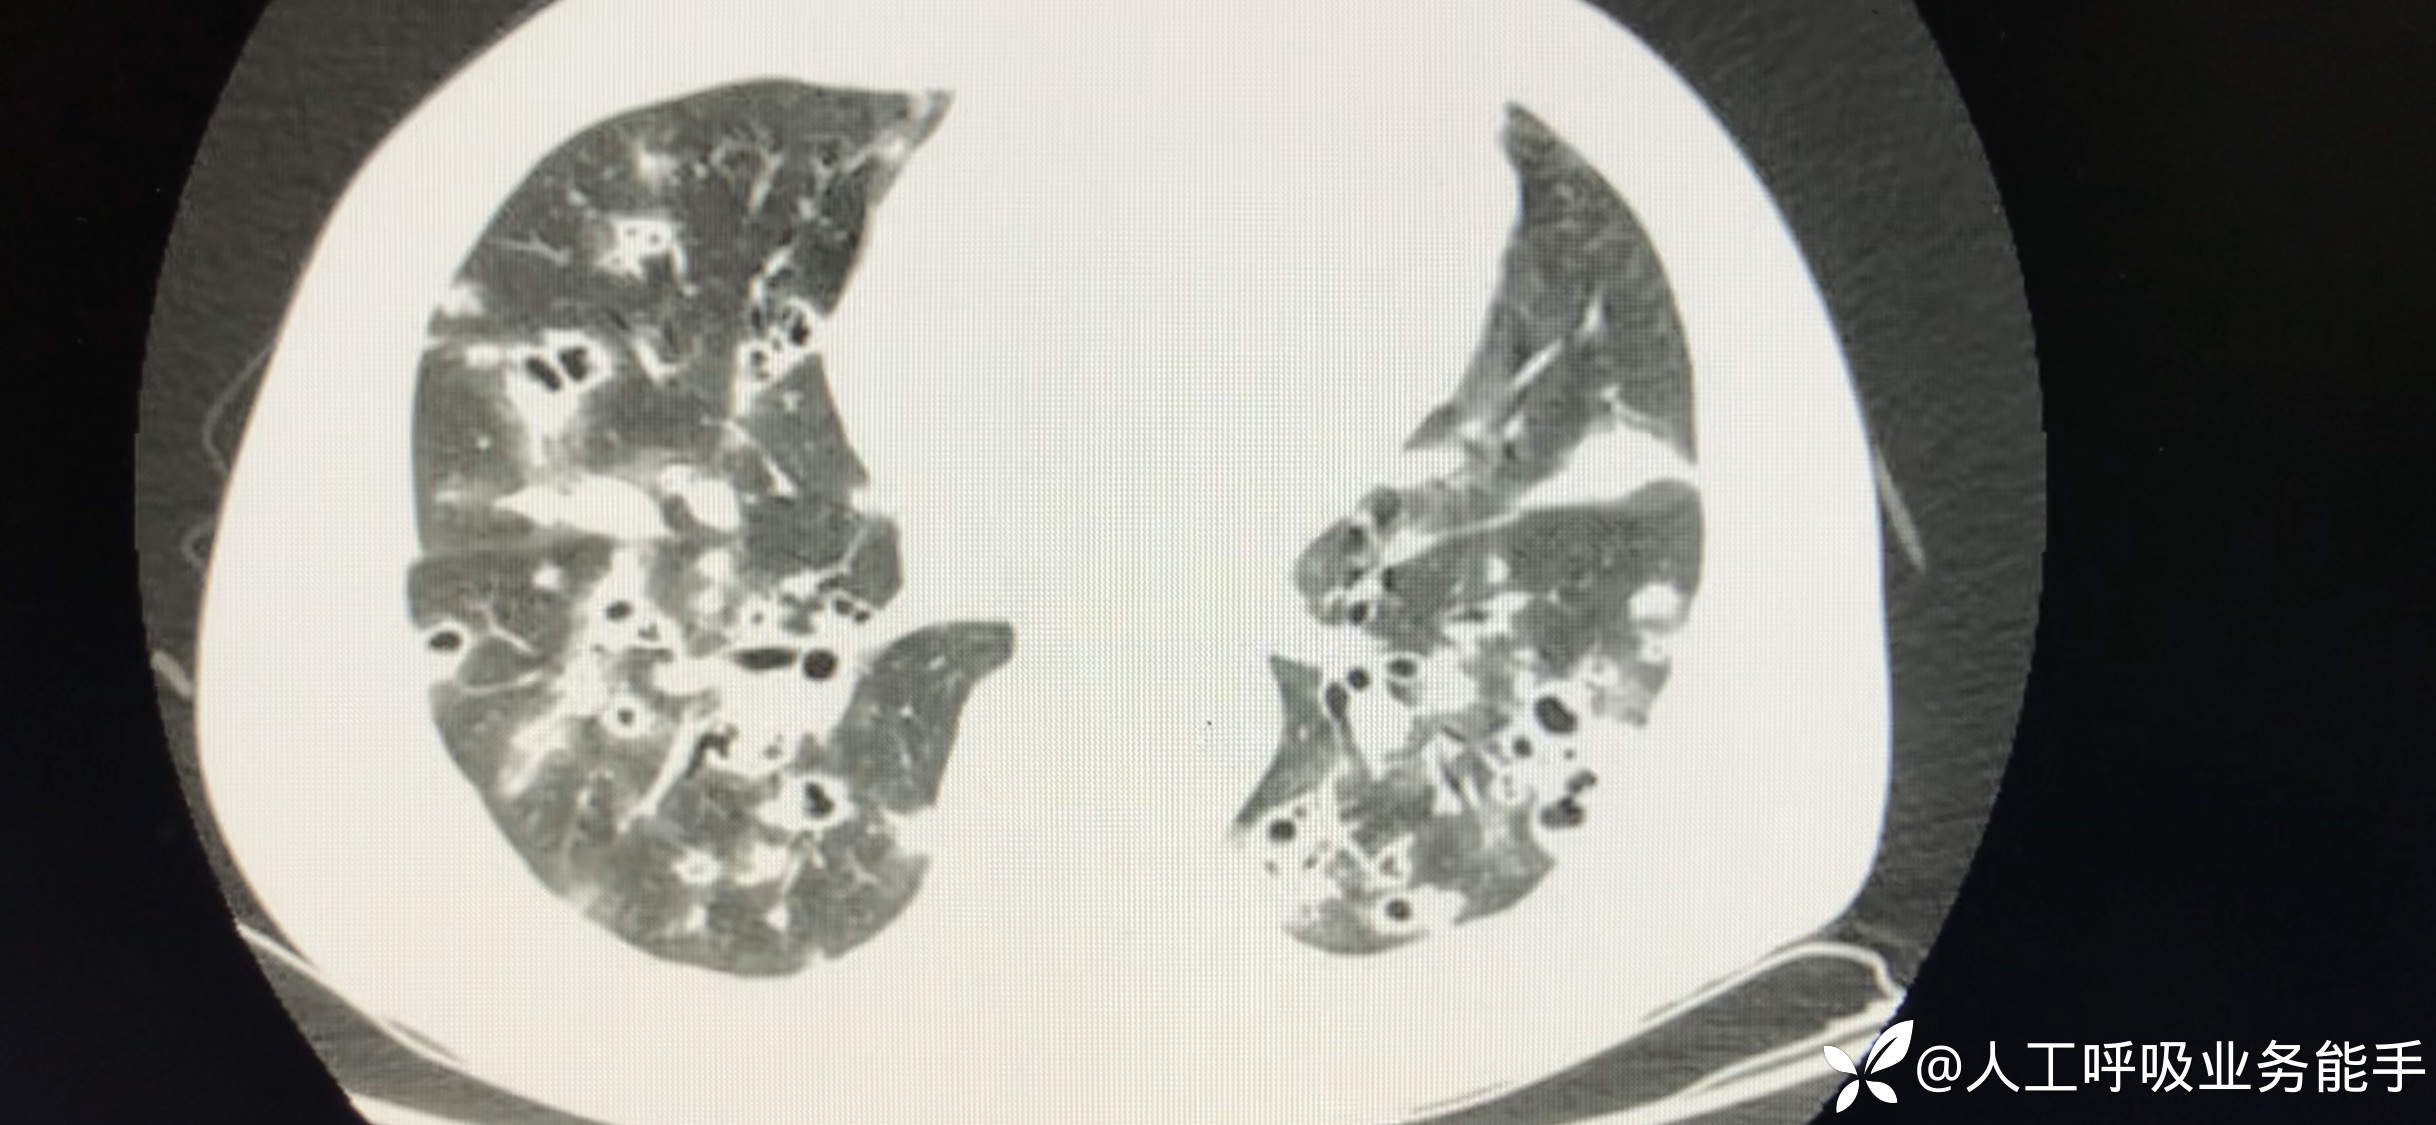

初诊影像: